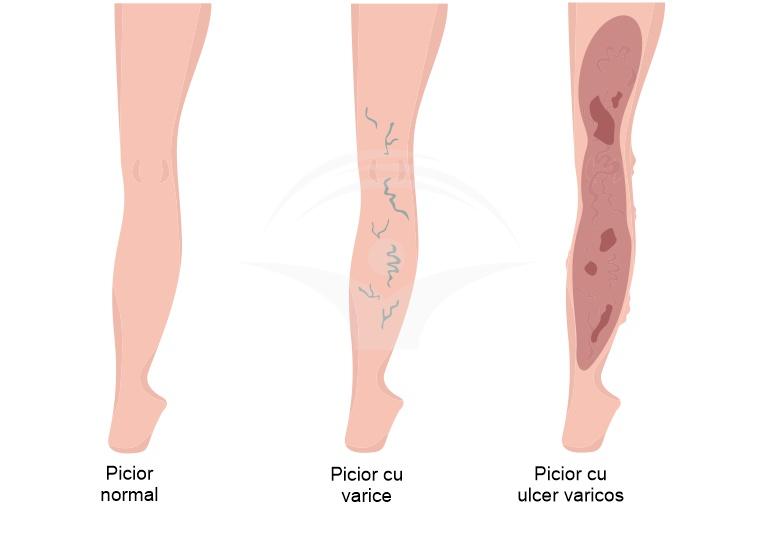

Leziunea deschisă care apare frecvent pe porţiunea inferioară a gambei este legată, în principal, de creşterea presiunii venoase şi de afectarea circulaţiei venoase. Acest proces favorizează inflamaţia, edemul şi fragilizarea pielii, iar vindecarea poate fi lentă, cu secreţie, durere şi modificări ale culorii şi texturii tegumentului; insuficienţa venoasă cronică este adesea un factor contribuabil important.

La nivelul pielii apar, de obicei, leziuni superficiale persistente, cel mai frecvent pe porțiunile inferioare ale piciorului; acestea pot avea margini neregulate, exsuda lichid și să fie însoțite de durere, senzație de arsură sau mâncărime. În jurul ulcerului pielea poate deveni îngroșată, hiperpigmentată sau edematoasă, iar supurația sau mirosul neplăcut pot semnala o suprainfecție; manifestările pot varia în intensitate și evoluție, uneori with perioade de remisie și recurență.

Simptomele asociate includ senzație de greutate sau oboseală la nivelul membrelor, crampe nocturne și prezența venelor varicoase vizibile, care pot contribui la întârzierea vindecării. Dacă observați semne de agravare, creșterea durerii, creșterea secreției sau semne sistemice, consultați un specialist pentru evaluare; pentru informații suplimentare, puteți căuta resurse legate de ulcer varicos. Manifestările pot diferi între persoane; doar un profesionist poate evalua corect tabloul clinic.

Ulcerul varicos apare frecvent în contextul unor tulburări venoase cronice care pot favoriza creșterea presiunii în venele membrelor inferioare și stagnarea sângelui. Factori precum varicele, insuficiența venoasă cronică, antecedente de tromboză venoasă profundă sau traumatisme locale pot contribui la apariție, iar condiții sistemice precum obezitatea, sedentarismul prelungit, sarcina și fumatul pot crește probabilitatea. De asemenea, boli care afectează vindecarea – cum ar fi diabetul sau arteriopatia periferică – pot complica evoluția și pot întârzia recuperarea.